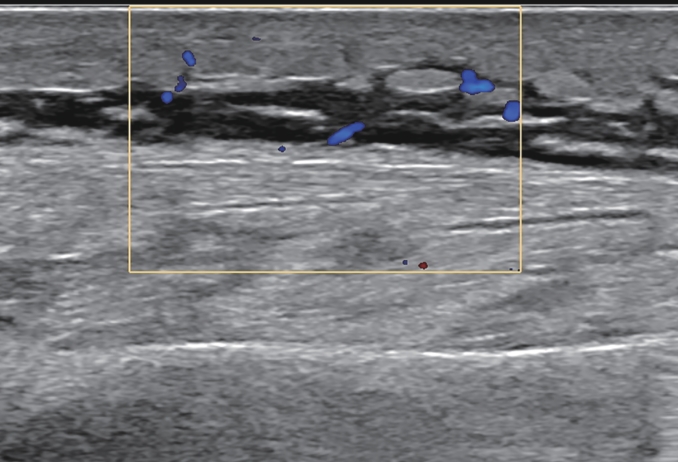

Correlation between liver fibrosis degree and carotid plaque in patients with lean metabolic dysfunction-associated fatty liver disease

Shuai ZHANG, Shoulu JIN, Wanqing LI, Xijing SHI, Hao LIANG, Hao DONG, Dailong LU, Ying ZHU, Xiaoxing XIANG, Jun LIU

2026, 42(2): 319-325. DOI: 10.12449/JCH260212

Abstract(111) HTML (30) PDF (3293KB)(56)

Abstract:

Objective  To investigate the association between noninvasive liver fibrosis markers and carotid plaque (CP) in patients with lean metabolic dysfunction-associated fatty liver disease (MAFLD), and to provide a basis for screening high-risk populations.  Methods  A total of 957 patients with lean MAFLD who underwent physical examination in Subei People’s Hospital from January 2021 to June 2023 was enrolled as the observation cohort, with the presence or absence of CP as the outcome, and fibrosis-4 (FIB-4) index and nonalcoholic fatty liver disease fibrosis score (NFS) were used to assess liver fibrosis degree. The independent-samples t test was used for comparison of normally distributed continuous data between two groups, and the Mann-Whitney U test was used for comparison of non-normally distributed continuous data between two groups; the chi-square test was used for comparison of categorical data between two groups. The multivariate logistic regression analysis, the restricted cubic spline analysis, the receiver operating characteristic curve, and the mediation effect analysis were used to investigate the association between liver fibrosis degree and CP.  Results  The prevalence rate of CP was 36.6% in the lean MAFLD population. Compared with the non-CP group(n=607), the CP group (n=350) had a significantly higher proportion of male patients, a significantly higher proportion of patients with smoking/diabetes/hypertension, and significantly higher levels of age, creatinine, blood urea nitrogen, triglycerides, fasting blood glucose, aspartate aminotransferase, aspartate aminotransferase/alanine aminotransferase ratio, NFS, and FIB-4 index, as well as significantly lower levels of platelet count and albumin (all P<0.05). The multivariate logistic regression analysis showed that after adjustment for confounding factors, FIB-4 index (odds ratio[OR]=2.979, 95% confidence interval[CI]:2.141 — 4.219, P<0.001) and NFS (OR=1.747, 95%CI: 1.499 — 2.046, P<0.001) were positively correlated with CP. Both FIB-4 index and NFS had a good value in predicting CP. Hypertension had a significant indirect effect on the prevalence rate of CP through its impact on liver fibrosis markers, and its mediating effect accounted for 39.5% — 40.8% of the total effect (P<0.001).  Conclusion  In patients with lean MAFLD, NFS and FIB-4 index are significantly positively correlated with the prevalence rate of CP, and they can be used as potential epidemiological predictive indicators. Liver fibrosis markers may play a mediating role in the association between hypertension and CP. Interventions targeting hypertension and liver fibrosis markers may help to prevent and delay the progression of CP.